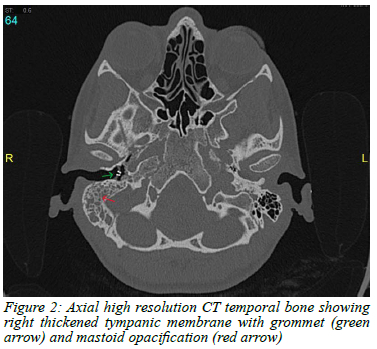

Case 2- A female in her early 20s presented with a 5-month history of right ear blockage, intermittent tinnitus and dizziness, and ipsilateral mild-to-moderate CHL (50 dB) confirmed on pure-tone audiometry (PTA). On initial presentation she had right-sided otitis media with an effusion (OME) with no symptoms suggestive of pulmonary TB and a clear chest X-ray. Her OME was treated with myringotomy and grommet insertion through a markedly thickened TM. High-resolution CT (HRCT) imaging revealed soft tissue opacification of the middle-ear cavity and mastoid antrum with slight erosion of the mastoid tegmen and a thickened, retracted TM (Figure 2). Both the ossicular chain and Prussak space appeared preserved. These findings were in keeping with chronic right otomastoiditis, rather than a cholesteatoma, and she required an exploratory tympanotomy and cortical mastoidectomy.